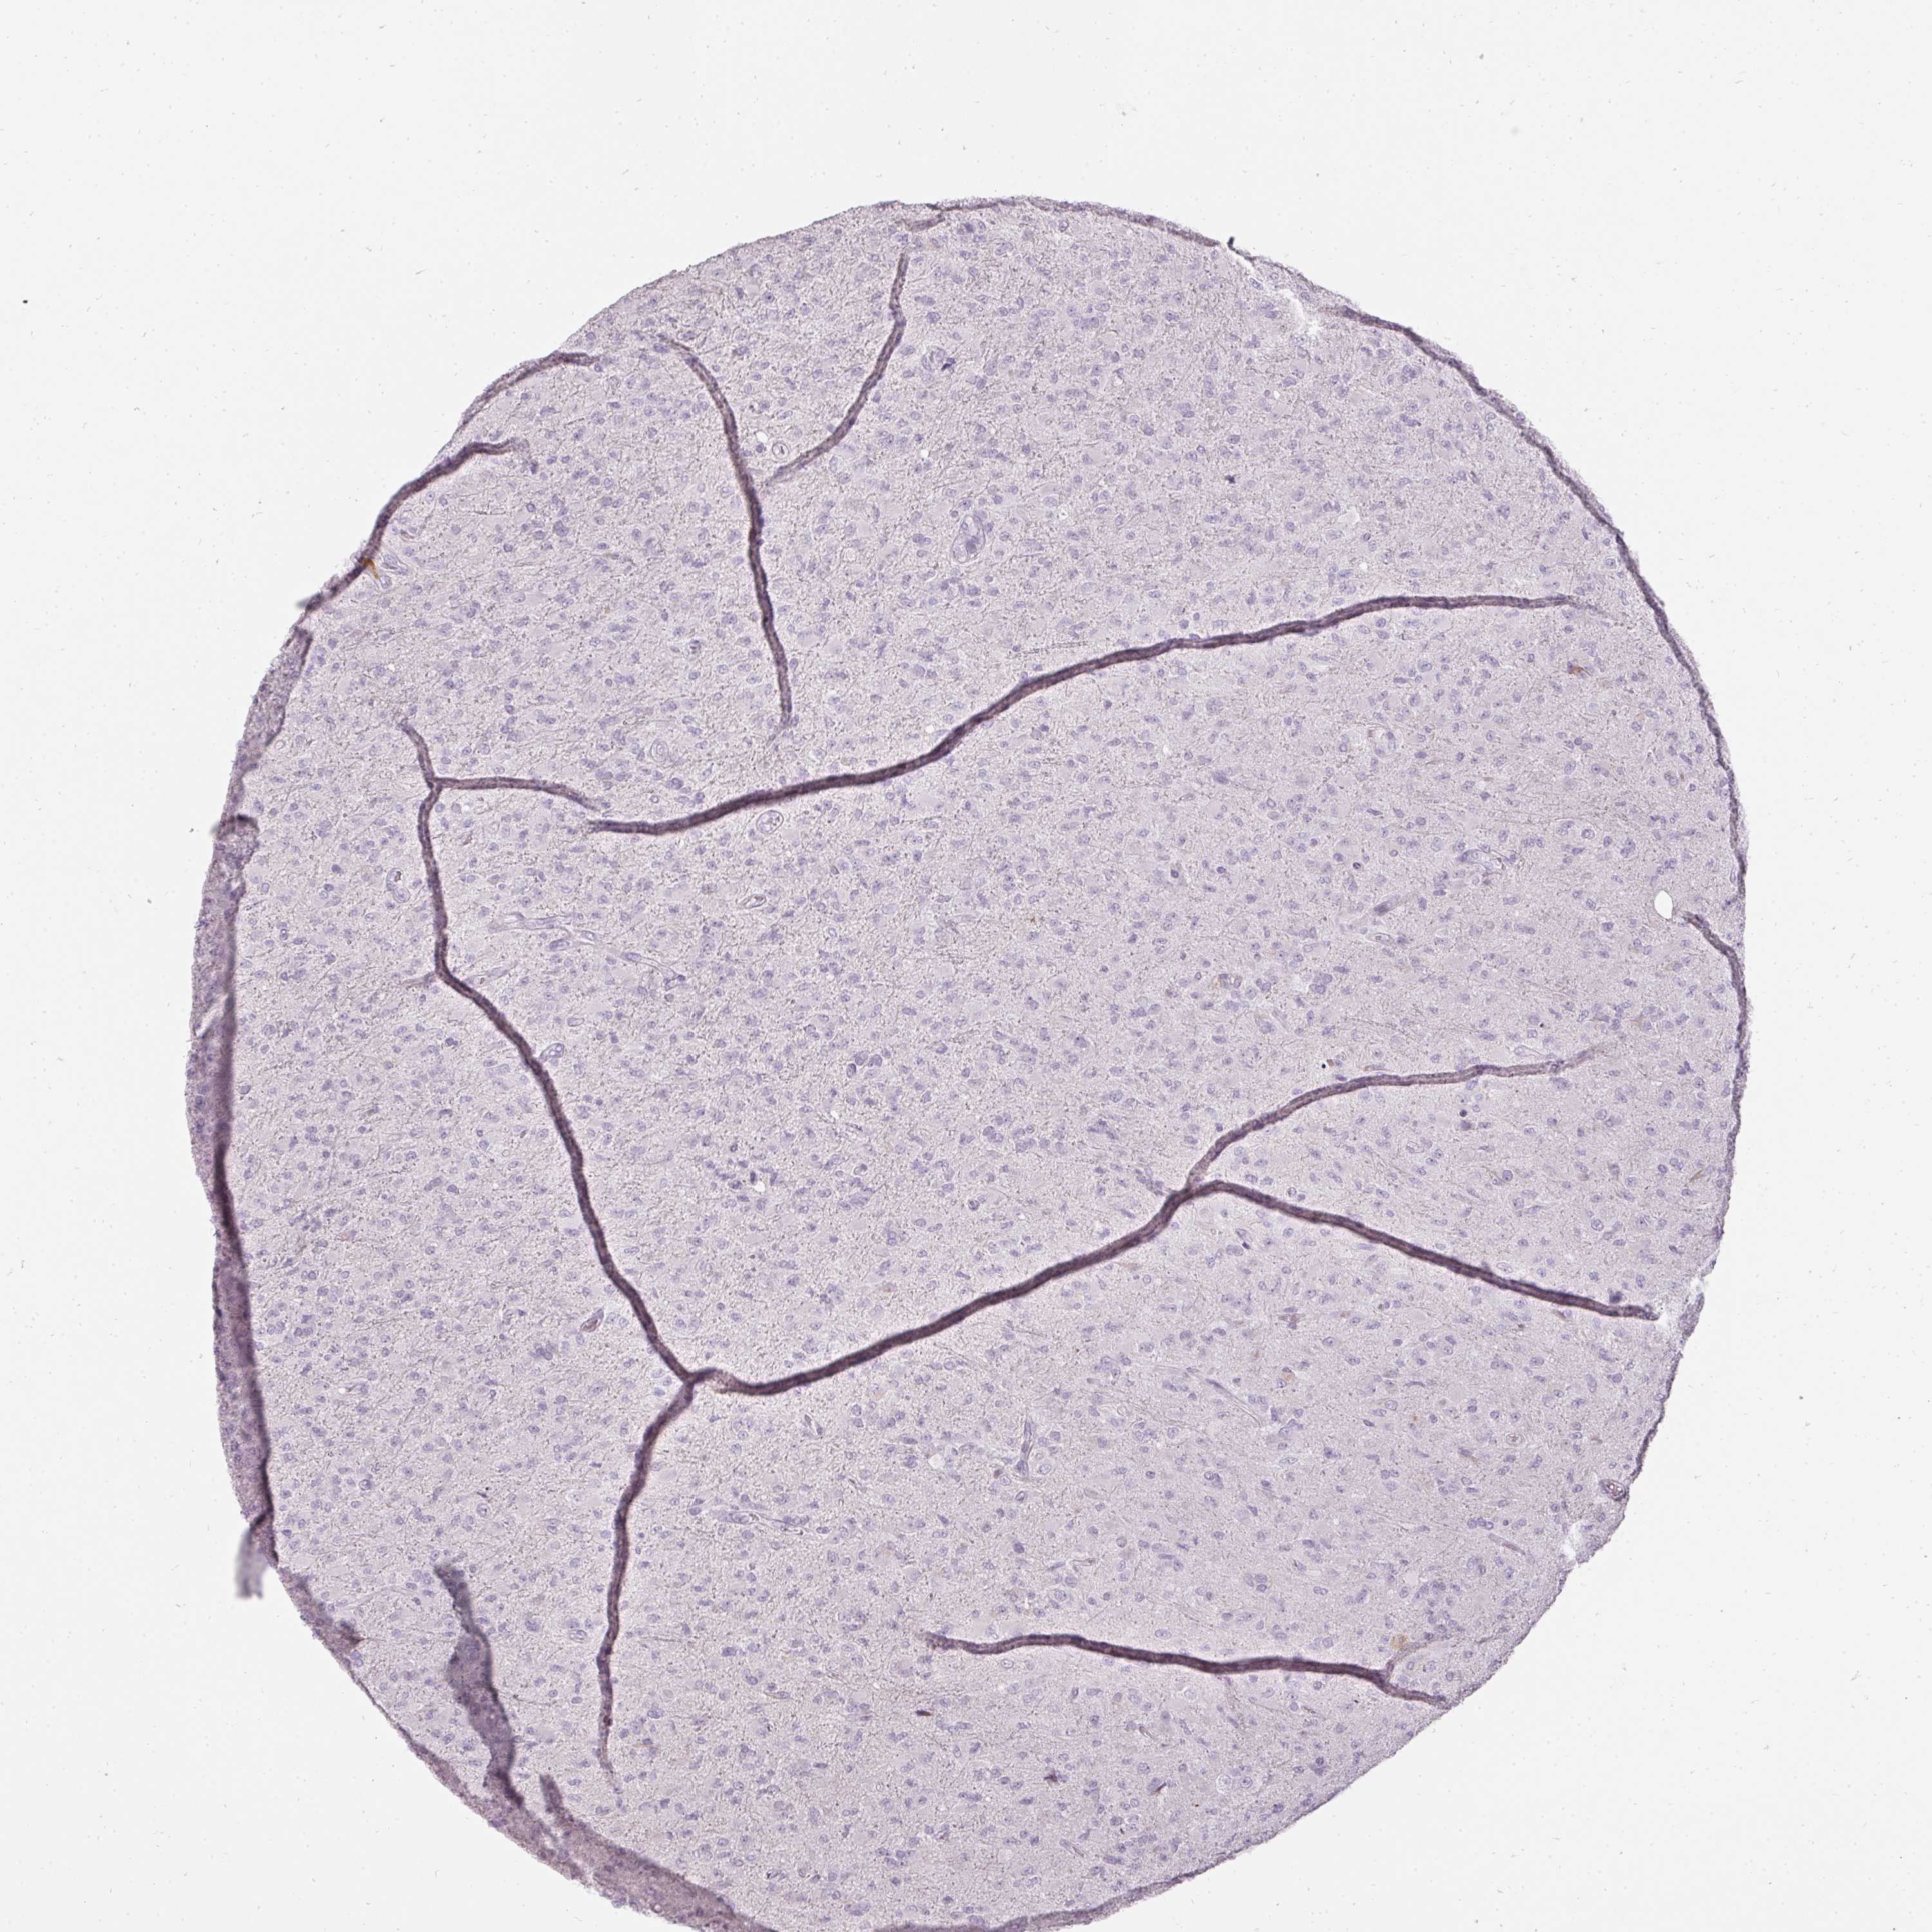

GLIOMA - Protein expressioni

A mouse-over function shows sample information and annotation data. Click on an image to view it in a full screen mode. Samples can be filtered based on level of antibody staining by selecting one or several of the following categories: high, medium, low and not detected. The assay and annotation is described here.

Note that samples used for immunohistochemistry by the Human Protein Atlas do not correspond to samples in the TCGA dataset.

Antibody stainingi

Antibody staining in the annotated cell types in the current human tissue is reported as not detected, low, medium, or high, based on conventional immunohistochemistry profiling in selected tissues. This score is based on the combination of the staining intensity and fraction of stained cells.

Each image is clickable and will lead to virtual microscopy that enables deeper exploration of all samples and also displays staining intensity scores, fraction scores and subcellular localization as well as patient and tissue information for each sample.

Antibody HPA051360

Staining

High

Medium

Low

Not detected

Intensity

Strong

Moderate

Weak

Negative

Quantity

>75%

75%-25%

<25%

None

Location

Nuclear

Cytoplasmic/membranous

Cytoplasmic/membranous,nuclear

Glioma, malignant, High grade

Glioma, malignant, Low grade